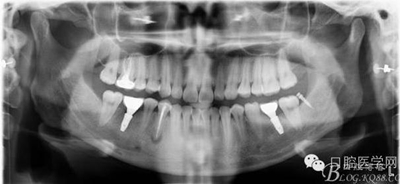

戴牙后忘記拍口內(nèi)照片了,只有一張X片,下次復(fù)診在補(bǔ)拍 44患者不愿冠修復(fù)

去除了支抗釘,要求患者3個(gè)月復(fù)查。